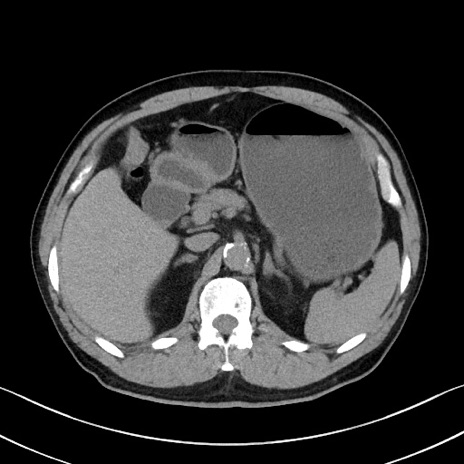

症例35(横断像)

【症例】70歳代 男性

【主訴】腹部膨満、嘔吐

【現病歴】昨日より腹部膨満感出現。本日増悪し、仙痛出現。嘔吐あり、受診。

【既往歴】糖尿病、胆摘後

【身体所見】BP 149/80mmHg、HR 74/min、BT 35.9℃、腹部:膨満、軟、圧痛なし。腸雑音減弱あり。上腹部正中切開瘢痕あり。

【データ】WBC 13500、CRP 1.72